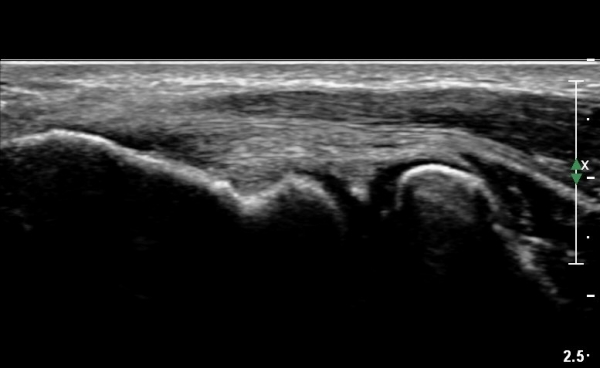

ŽÃËÀÚ¸¦ ¾à°£ ¿ÜÃøÀ¸·Î À̵¿ÇÏ´Ï °Ë ºÎÂøºÎ¿Í ÀÎ´ë ºÎÂøºÎÀÇ  ¹Ì¼¼ÇÑ ÆÄ¿­ÀÌ °üÂûµÈ´Ù(»çÁø 3).